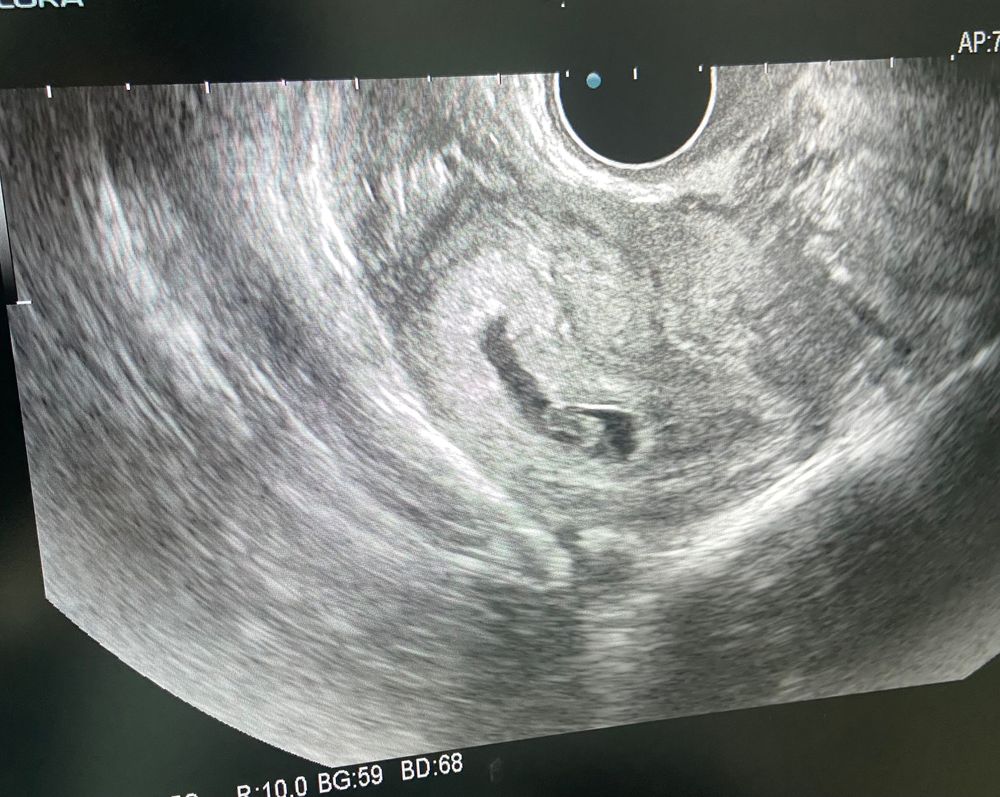

Узи 7 недель

2е узи

Сердечко бьется❤️на экране прям видно было-это очень трепетно

по М срок: 7нед3дня

по узи отстает 6н4дня,более точно уже будем на скрининге ориентироваться

КТР 7.2мм

Размер ПЯ: 19мм

желточный мешок 3.3мм

Растем дальше.Продолжаем пить Дюфастон. Становимся на учет и ждём 1 скрининга🥰